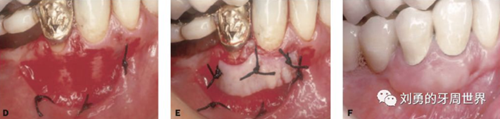

比如下面兩張圖就分別是縫合和剪掉的方法: